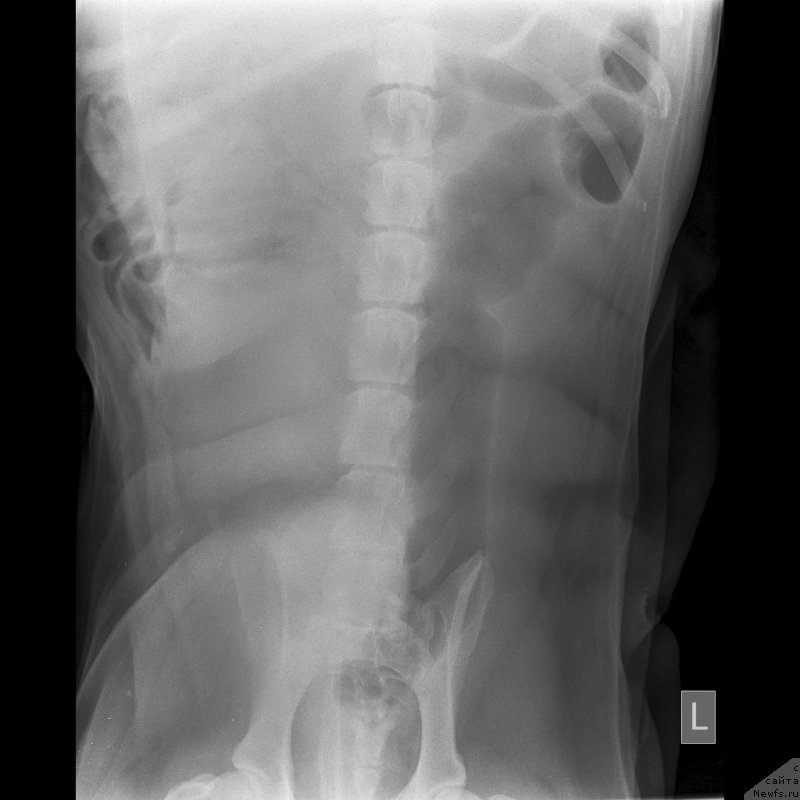

Второй ветеринар сделал ренген, где ничего не видно кроме начинающегося артроза.Опасения что слопал кость-отмели.

Сделали цифровой рентген в соседнем городе(Темиртау).Сейчас постараюсь его выставить.На мой взгляд не очень удачный.завтра наверное переделаем.

По клинической картине и по снимкам - спондилёз поясничного отдела позвоночника. Лечение: первые сутки дексаметазон 4 мг 3 раза /день или преднизолон, можно внутримышечно, и римадил 100мг 3 раза в день.